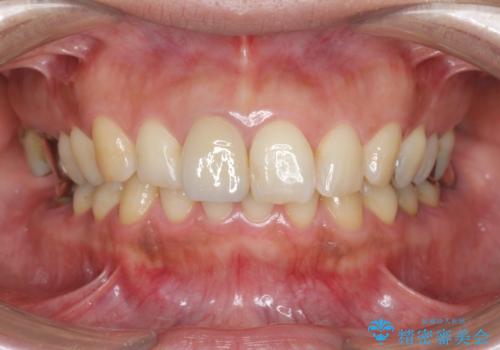

破折リスクを少なくするため前歯でかじったり硬いものを噛み切る等の行為は避けた方が良いとお伝えし、現状5年問題なく経過しています。

セラミック治療の注意事項(リスク・副作用など)

- かみ合わせや歯ぎしりが強すぎる方はセラミックが割れてしまう可能性があります